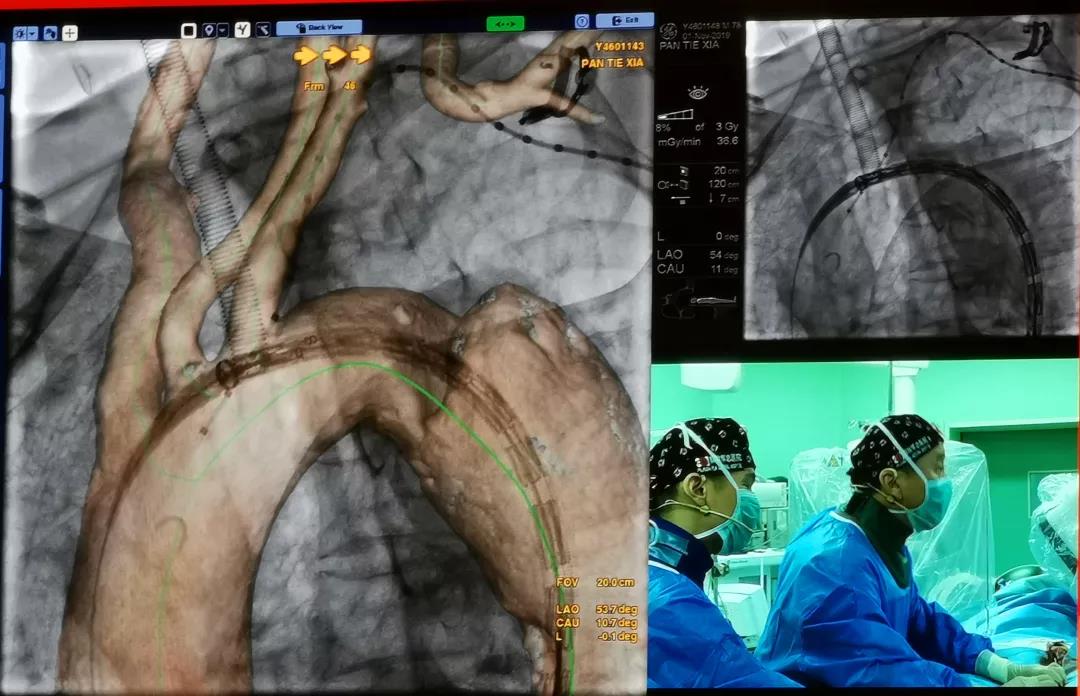

中国人民解放军总医院郭伟教授共演示了3台手术,分别是采用Ankura™支架治疗Stanford B型慢性胸主动脉夹层,采用Lifeflow™IBD髂动脉分叉支架系统和Fustar™可调弯鞘在治疗腹主动脉瘤时重建右侧髂内动脉的病例。另外,郭伟教授还演示了一台使用Ankura™支架和新型G-Branch™胸腹主动脉覆膜支架系统重建内脏动脉全腔内修复胸腹主动脉瘤的病例。郭教授从患者病变情况和治疗难点、手术方案、G-Branch™支架产品设计特点及术中操作要点等方面详细介绍了手术过程。手术取得了极大的成功,术后造影显示,瘤体隔绝,内脏四分支血管血流通畅,且主体支架与分支支架连接处无内漏。与会专家对此精彩的病例表示尤为赞叹,积极与郭伟教授探讨G-Branch™支架的创新之处和未来使用方向。郭教授表示,多分支动脉的腔内重建是胸腹主动脉瘤微创治疗的一个技术高地,也是国际性难题。G-Branch™支架的应用,为胸腹主动脉瘤的患者提供了更为优秀的解决方案,期待未来更多的临床应用和循证医学证据将证实其优越性。

中国人民解放军总医院手术直播《Ankura™支架腔内修复胸主动脉夹层》

中国人民解放军总医院手术直播《Lifeflow™ IBD支架在腹主动脉瘤的腔内修复术中的应用》

中国人民解放军总医院手术录播《G-Branch™多分支支架治疗胸腹主动脉瘤》